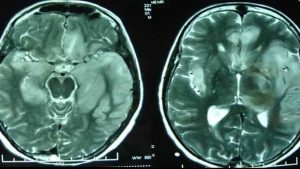

Thiếu oxy lên não nguy hiểm như thế nào ?

Thiếu oxy lên não là một tình trạng nguy hiểm của thiếu máu lên não. Hiện tượng này có thể dẫn đến những biến chứng nguy hiểm nếu không được điều trị kịp thời. Vậy thiếu oxy não là gì? Nguyên nhân của thiếu oxy lên não và nó nguy hiểm ra sao ? Phương […]